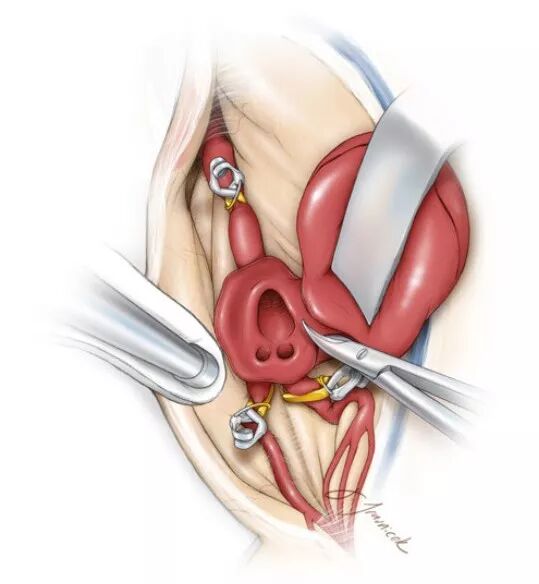

图11. 通常情况下笔者并不切开瘤囊,而选择直接夹闭。然而,有一部分动脉瘤需切除部分瘤壁以达到暴露瘤颈和减压之目的(引自Tew,van Loveren,Keller)。

![]()

图12. 切除瘤壁时勿离M1流入道和M2流出道太近,保留足够的瘤壁组织,以备关闭瘤口时于二分叉处重建一个囊袋状结构(引自Tew,van Loveren,Keller)。